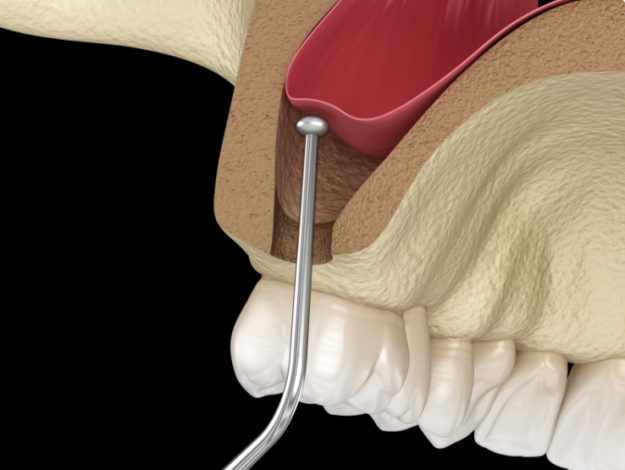

Elevación del seno maxilar: ¿Qué es y en qué consiste?

Al momento de hacer una colocación de implantes dentales 🦷hay muchos factores que hay que tener en cuenta, uno de ellos es el seno maxilar. La elevación del seno maxilar es un proceso complejo, si quieres saber en qué consiste hoy desde Clínica Dental Albea en Bilbao te contamos todos los detalles. ¡Sigue leyendo!👇 ¿Qué es una…